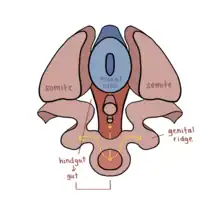

Sex cords are embryonic structures which eventually will give rise (differentiate) to the adult gonads (reproductive organs).[1] They are formed from the genital ridges - which will develop into the gonads - in the first 2 months of gestation (embryonic development) which depending on the sex of the embryo will give rise to male or female sex cords.[2] These epithelial cells (from the genital ridges) penetrate and invade the underlying mesenchyme to form the primitive sex cords.[3] This occurs shortly before and during the arrival of the primordial germ cells (PGCs) to the paired genital ridges.[3] If there is a Y chromosome present, testicular cords will develop via the Sry gene (on the Y chromosome): repressing the female sex cord genes and activating the male.[4][5] If there is no Y chromosome present the opposite will occur, developing ovarian cords.[6][7] Prior to giving rise to sex cords, both XX and XY embryos have Müllerian ducts and Wolffian ducts.[2] One of these structures will be repressed to induce the other to further differentiate into the external genitalia.[2]